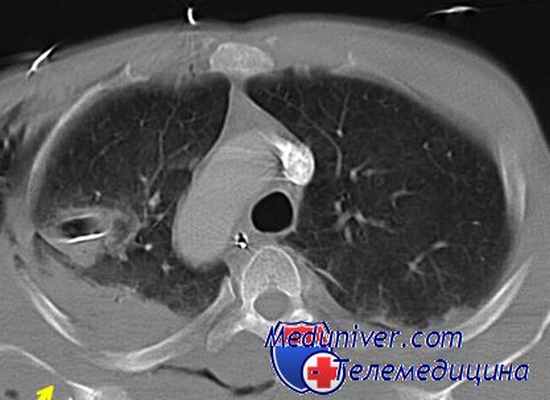

15 Диагностика Рентгенологическое исследование. При рентгенографии тень неврогенных опухолей определяется в реберно-позвоночном углу, внутренний контур сливается с тенью средостения, наружный - хорошо прослеживается на фоне легочного поля. Тень опухоли, даже при многоосевой рентгеноскопии, отделить от позвоночника не удается. Неврогенные опухоли дают округлую довольно плотную тень, часто с мелкими включениями, особенно при опухолях симпатической нервной системы (от 15 до 20%). При подозрении на неврогенную опухоль рентгенограммы необходимо делать различной жесткости, что может выявить имеющиеся изменения со стороны позвоночника и ребер, к которым прилегает опухоль. Нередко определяется узурпация, атрофия ребер и расширение межреберных промежутков.

16 При диагностических затруднениях необходимо применять дополнительные методы исследования, наиболее ценными из них являются: томография, рентгенография с пневмотораксом, пневмомедиастинография.

Чаще всего, как и при других опухолях этой локализации, выражены рентгенологические признаки. Обычно на рентгенограммах видна овальной или округлой формы интенсивная, гомогенная тень, имеющая четкие контуры, располагающаяся чаще всего в задневерхних отделах средостения. Медиальная часть этого образования сливается со средостением, латеральная хорошо заметна, особенно после наложения искусственного пневмоторакса.